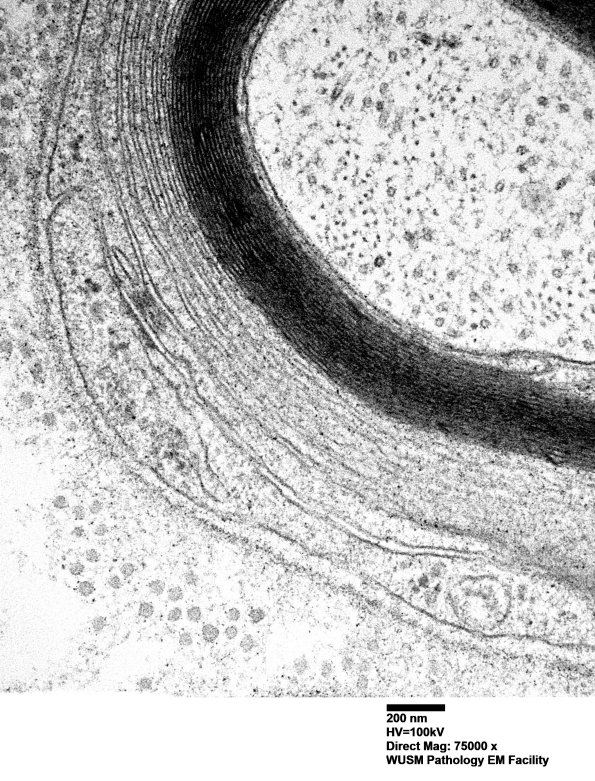

Higher magnification of image #2C1B. (electron micrograph)